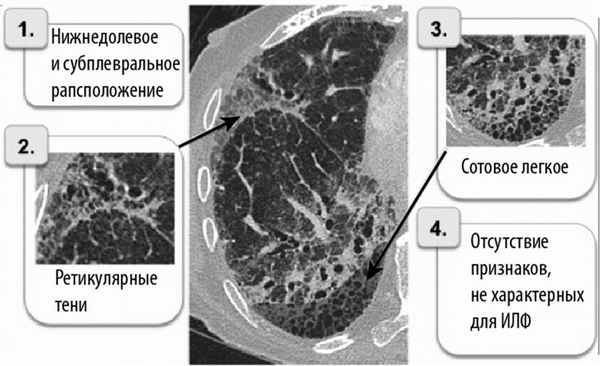

— Для выделения ИФЛ из группы других идиопатических ИБЛ основным ориентиром служат результаты КТ легких высокого разрешения [4] (рис. 2).

Рис. 2. Главные компьютерно-томографические признаки ИФЛ.

В соответствии с диагностическими признаками ИФЛ по данным КТ выделяют 3 категории вероятности наличия у больного ИФЛ [4]:

— субплевральное расположение в нижних долях;

— сотовое легкое ± тракционные бронхоэктазы;

— отсутствие признаков несоответствия.

• КТВР/КТ:

о Ретикулярные изменения с преимущественным поражением базальных отделов

о Тракционные бронхо-/бронхиолоэктазы

о «Сотовое легкое»

о «Матовое стекло» (менее распространенное, чем ретикулярные изменения)

• Идиопатические ретикулярные изменения в субплевральных и базальных отделах наряду с «сотовым легким» позволяют диагностировать ИЛФ на КТВР